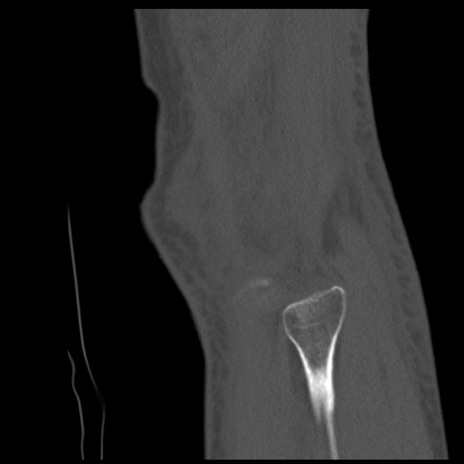

症例28 右膝関節CT(矢状断像)

右膝関節CT